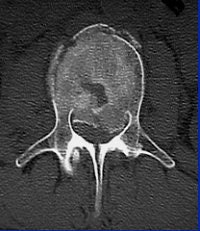

![]() ![]() |

"With CT, you see that it's not just a compression fracture of the superior endplate, but really it's a burst fracture involving the anterior, middle, and posterior columns. The fracture goes through the vertebral body (with) retropulsion of bone, and it goes through the spinous process, through the lamina, and even into the facet joint."